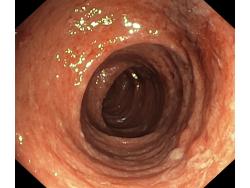

Zapalenie wrzodziejące...

Zapalenie wrzodziejące jelita grubego